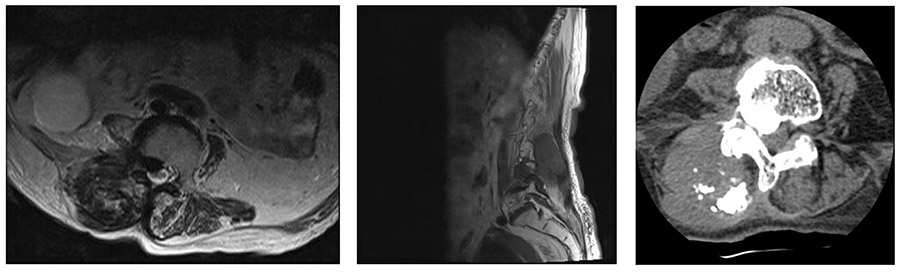

Ameliyat Öncesi: MR’da düzensiz sınırlı heterojen kitle, tomografide kitle içi kalsifikasyonlar saptandı